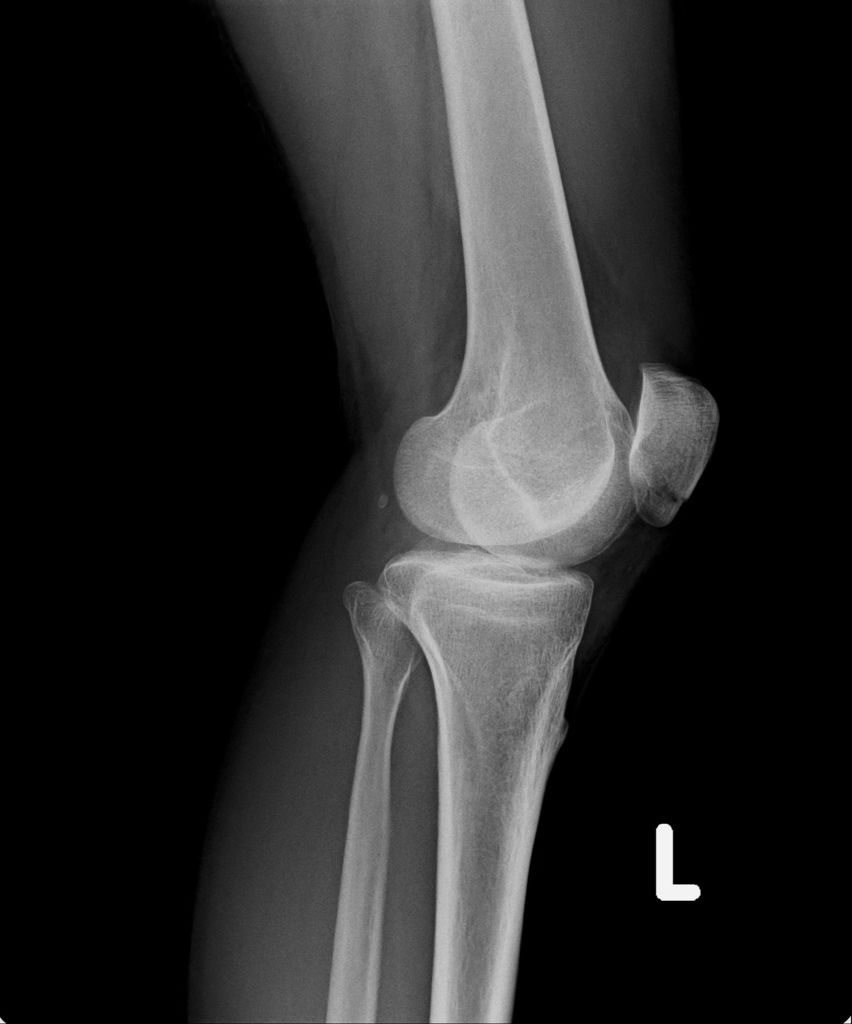

下午,小純陪我去澄清醫院回診,黃醫師看了我右手的情形,以及所能彎曲的角度,對我說:「你復原的很慢喔。」叫我回家一定要拗手,還說:「你自己要拗,我也不能每天都去你家幫你拗呀。」看到我被拗露出痛苦的神情時,還跟我說:「回去自己拗,好好的折磨自己吧。」

之後,我去照了X光,因為一個月前照X光,感覺已經快好了,我以為今天去照,骨頭應已癒合的差不多了。結果照出來之後,竟然還能看的到裂痕,讓我大吃一驚。唉....可能要等一陣子才會好。

今日所拍攝的X光照↓

最近四次所拍的X光↓